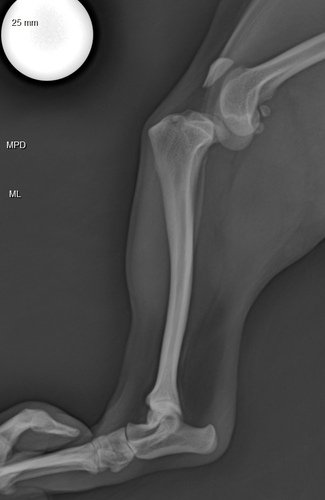

Olá Aumigos! Minha cachorrinha vai precisar passar por uma cirurgia de luxação de patela + ruptura de ligamento Desde o dia 13/07/2024, minha cachorrinha começou a mancar então levamos ela ao veterinário no qual doi diagnóstico clinicamente é comprovado pelos exames esse problema na patela. 😭

TPLO Modificada R$ 3,100,00

Raio X Controle Ortopedico R$ 100,00

Tomografia R$ 1340,00